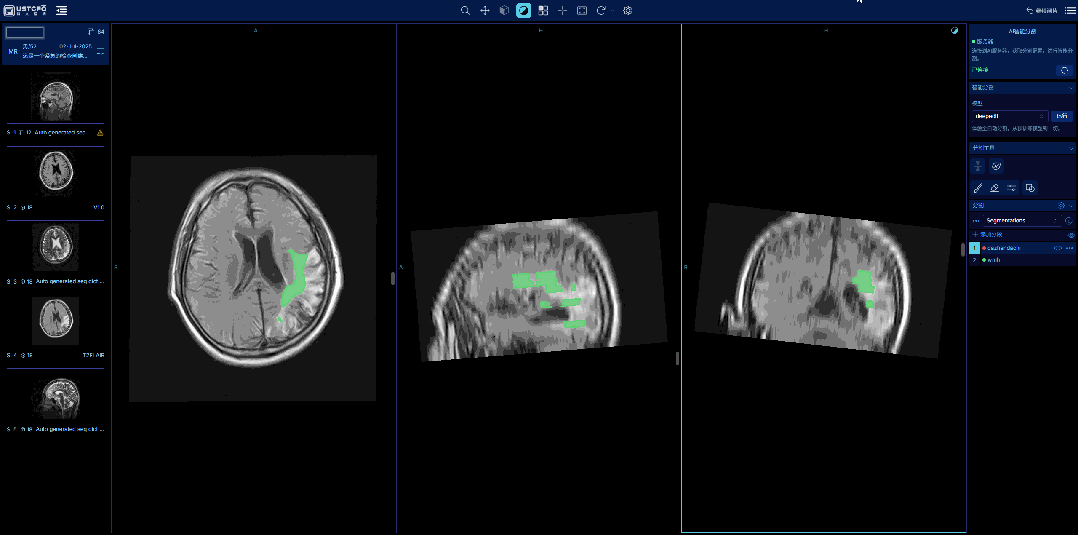

2、 AI智能分割:由福晴医疗通过在服务器端训练深度脑分割模型,实现AI智能分割功能。用户通过界面交互开启AI预分割,然后通过分割工具进行微调,通过分段实现不同区域的标注,最后保存为SEG文件,持续驱动模型优化升级。

模型通过持续学习用户标注意图,其智能分割的精度与理解能力不断提升。这不仅能显著降低新数据集的标注成本,更能让模型动态适应实际任务需求,实现越用越智能的分割体验。

1、 用户可以使用预训练的模型直接标记大枕大池区域和脑白质区域,并查看相关区域的参数。